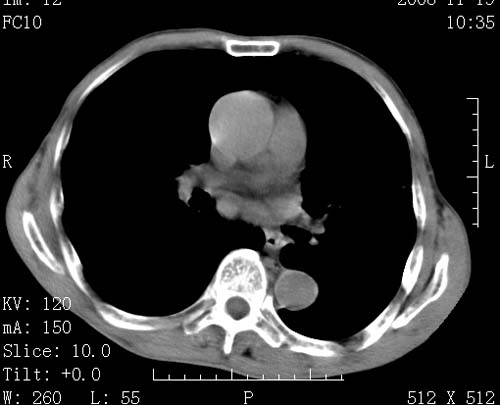

标题: CT16691:m 67 胃镜确诊食管下段及贲门癌 [打印本页]

标题: CT16691:m 67 胃镜确诊食管下段及贲门癌

术前查体,双肺部结节是转移?结核?请点评

1)符合食管癌表现。2)两肺及纵隔淋巴结多发性转移瘤。3)左肺上叶舌段及两肺下叶炎症感染。

食管癌伴双肺转移,评述:肺部毛细血管网丰富,全身血液均快速流经肺部,癌细胞容易过滤定植,形成转移瘤,影象特点为以毛细血管末梢为中心的结节灶,边缘光滑锐利,少见有中心空洞着,不同来源的转移瘤可有各自特点,如甲状腺癌为双肺弥漫性微结节,本例有原发灶,双肺影象灶典型,左肺舌段条带状网格样伴胸膜天幕征,可视为癌性淋巴管炎。

左肺舌段有斑点钙化灶,能否说明是结核而不是转移?如果是转移将放弃手术改成化疗,如果是结核将考虑择期手术